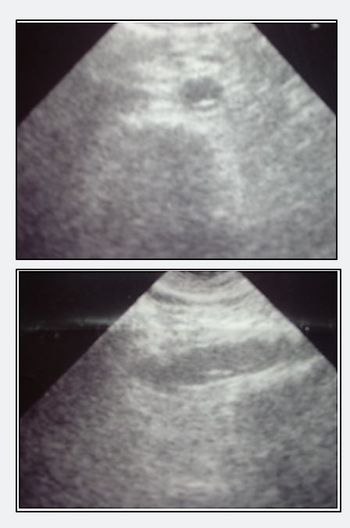

A 32-year-old man visits the ED for an oral canker sore that should have run its course but is getting worse. What one question should you ask?